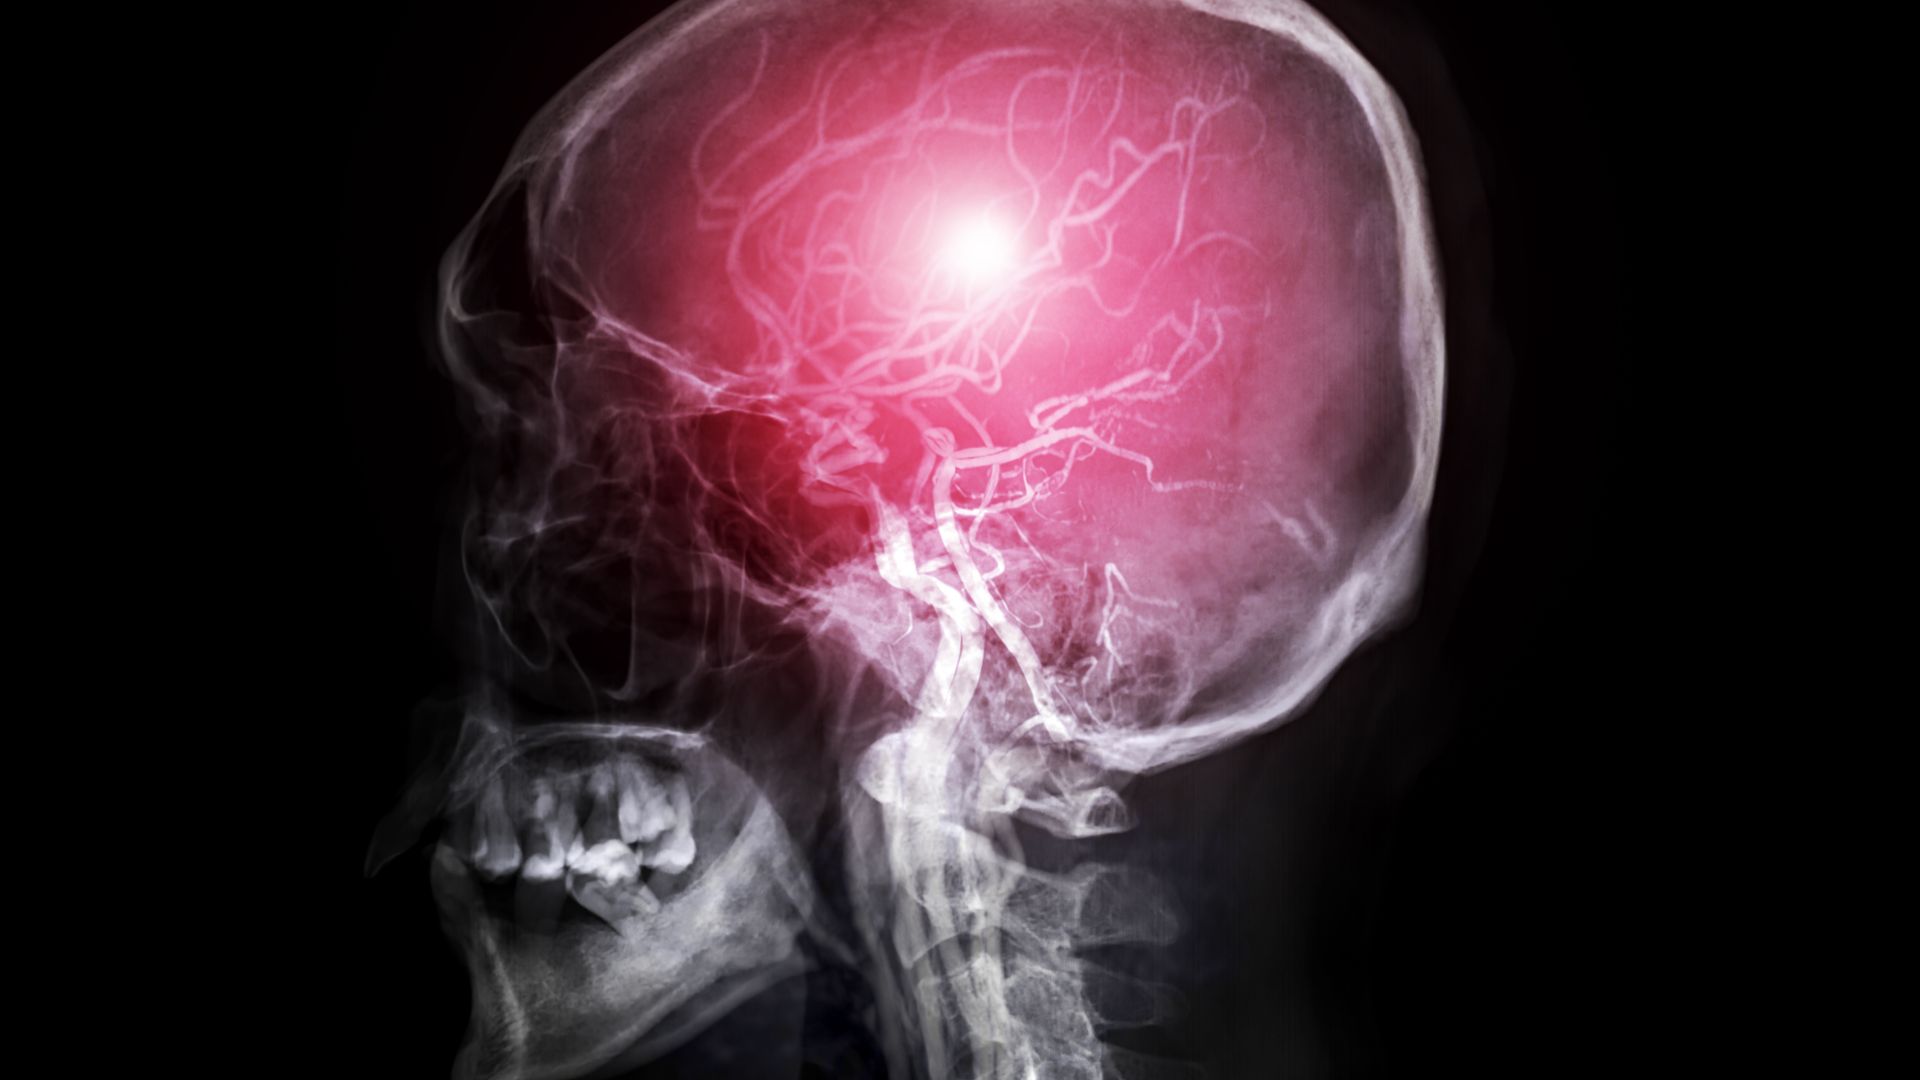

Thiếu oxy lên não xảy ra khi não bộ không nhận đủ lượng oxy để duy trì các chức năng sống cơ bản. Đây là tình trạng tiềm ẩn nhiều rủi ro, bởi chỉ trong vài phút thiếu oxy, các tế bào thần kinh đã có thể tổn thương không thể hồi phục. Nhiều báo cáo y khoa cho thấy thiếu oxy lên não liên quan trực tiếp đến các vấn đề như mất tập trung, suy giảm trí nhớ, rối loạn cảm xúc và thậm chí gây ra những biến chứng nguy hiểm nếu không được can thiệp kịp thời.

Thiếu oxy lên não thường bắt nguồn từ nhiều vấn đề sức khỏe khác nhau, trong đó nổi bật nhất là các bệnh lý mạch máu não và những tổn thương liên quan đến sọ não. Khi huyết áp giảm quá thấp hoặc tăng quá cao, dòng máu lên não có thể bị rối loạn, khiến lượng oxy cung cấp cho tế bào thần kinh không đủ. Bên cạnh đó, các bệnh về tim mạch và phổi cũng là nguyên nhân phổ biến, bởi tim yếu hoặc phổi hoạt động kém sẽ làm giảm hiệu quả vận chuyển oxy trong cơ thể.

Chấn thương sọ não, tổn thương khí quản hoặc phổi đều có thể làm gián đoạn quá trình hô hấp và tuần hoàn máu, từ đó dẫn đến thiếu oxy lên não. Một số bệnh lý đặc thù như xơ cứng teo cơ một bên, dị tật mạch máu bẩm sinh, hoặc các vấn đề ở đốt sống cổ như thoái hóa, thoát vị đĩa đệm có thể gây chèn ép mạch máu, làm giảm lưu lượng máu lên não và khiến não không nhận đủ oxy để hoạt động bình thường.